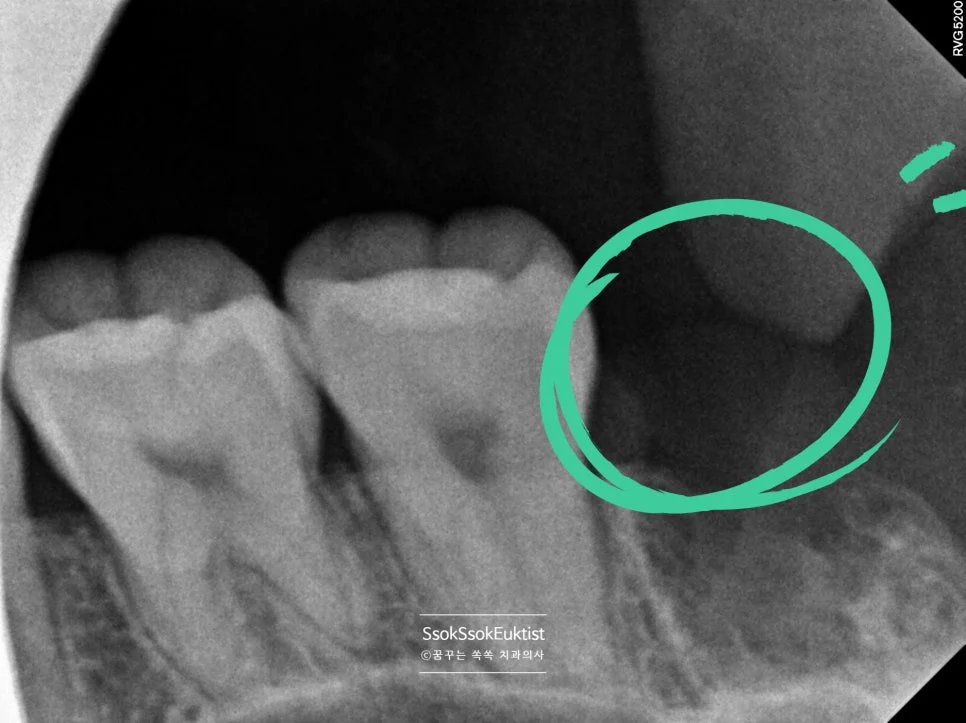

CBCT(3D CT)로 신경관 위치 확인

CBCT 우측 하악 매복 사랑니 신경관 근접도 분석

우측 CBCT — 신경관 근접도 분석

매복된 사랑니는, CT를 통해 신경관과 맞닿아 있진 않은지 정밀하게 분석 후 발치를 시도합니다.